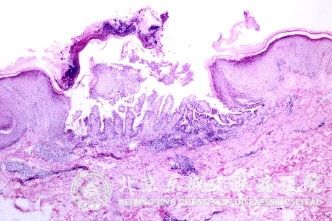

北京京城皮肤医院指出,牛皮癣又称银屑病,是红斑鳞屑疾病的一种,也是一种自身炎症性皮肤病,一般可发于全身各处,好发于裸露部位,主要有头部、四肢、前胸、后背等部位,虽不危及生命,但是临床上还没有治疗的方法。